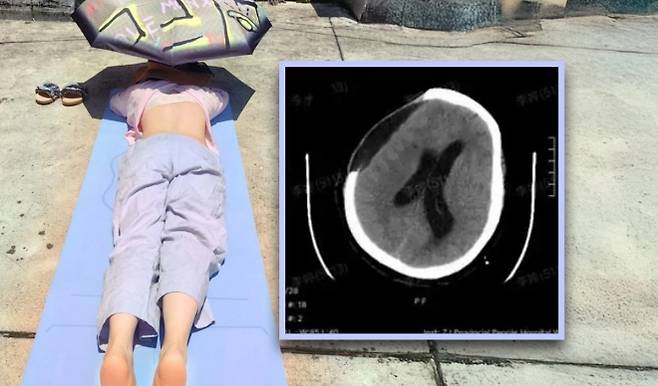

중국에서 장시간 일광욕을 즐기던 여성이 뇌출혈 증세로 쓰러져 혼수상태에 빠지는 일이 발생했다.

20일(현지시간) 홍콩 사우스차이나모닝포스트(SCMP)에 따르면 중국 저장성에 사는 왕모씨(67·여)는 최근 야외에서 일광욕을 즐기다 쓰러져 병원으로 이송됐다.

‘햇볕에 등을 쬐면 양기가 따뜻해지고 습이 빠져나가 각종 질병을 예방할 수 있다’는 민간요법에 따라 정오부터 두 시간 동안 땡볕에 엎드린 채 누워 있었던 게 화근이었다.

검사 결과 왕씨는 뇌동맥류성 뇌출혈과 뇌헤르니아(뇌탈출) 증상을 보였고, 의료진은 곧장 응급 수술에 들어갔다.

수술은 성공적이었지만 왕씨는 혼수상태에 빠졌다. 다행히 얼마 후 의식을 회복했으나, 스스로 움직이고 음식을 섭취할 수 있을 때까지 한동안 재활치료가 필요했다.

왕씨 사례에 대해 저장성 인민병원 재활의학과 예샹밍 주임은 “‘햇볕이 만병통치약’이라는 주장은 과학적 근거가 전혀 없다. 특히 고령자나 고혈압, 뇌혈관 질환이 있는 사람은 장시간 햇볕에 노출될 경우 열사병이나 뇌졸중 등 심각한 상황으로 이어질 수 있다”라고 경고했다.